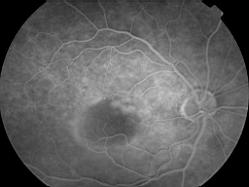

DMLA associant un DSNE et une plage de NVO